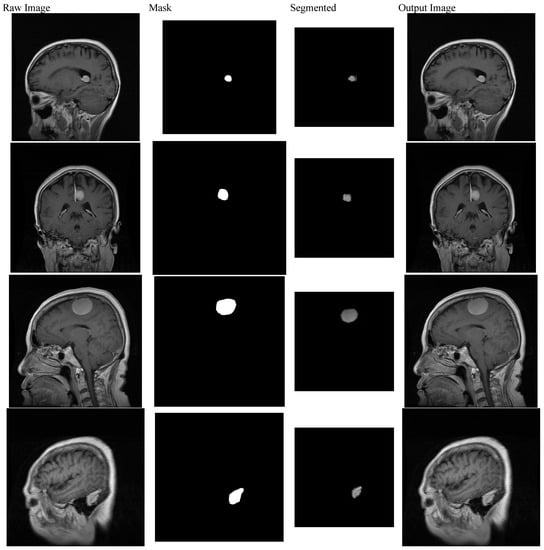

3. Background of Predictive Attributes for BM Classification

4.3. MtS Localization Employing NtNt Framework

4.4. MtS Area Segmentation Employing NtNt Framework